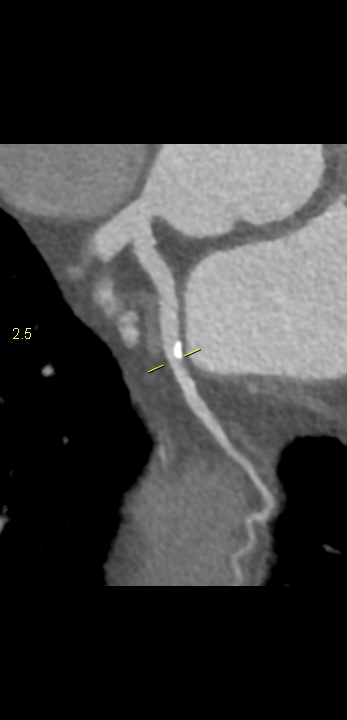

Figururile 1-9: reconstrucție în axul lung al vasului pentru arterele coronare cu evidențierea unui calibru global crescut la nivelul acestora și cu încărcătură ușoară-moderată de placă în principal calcificată

Discuţie caz nr 132: Examinările coroCT se efectuează în principal pentru aprecierea încărcăturii de placă precum și pentru evidențierea reducerilor de lumen ce necesită tratament. Această examinare a evidențiat creștere globală a calibrului arterelor coronare și o încărcătură ușoară-moderată cu placă în principal calcificată, fără a se evidenția arii de stenoză.

DE LUAT ACASĂ!!! Ectazia coronariană este o afecțiune rară caracterizată prin dilatarea anormală (diametrul vasului este de 1.5 ori mai mare) a arterelor coronare, care poate duce la afectarea fluxului sanguin și la un risc crescut de ischemie. Etiologia nu este cunoscută iar afecțiunea poate fi asociată cu ateroscleroză sau factori congenitali și reprezintă o provocare atât în diagnostic, cât și în tratament. Simptomele se suprapun adesea cu cele ale altor boli coronariene, ceea ce face ca identificarea timpurie să fie crucială. Opțiunile de tratament variază de la tratamentul medical cu terapie antiplachetară sau anticoagulantă până la proceduri intervenționale, cum ar fi angioplastia sau intervenția chirurgicală, în funcție de severitatea și riscul de complicații. Tratamentul pe termen lung se concentrează pe prevenirea evenimentelor ischemice și pe abordarea cauzelor care stau la baza acestora.